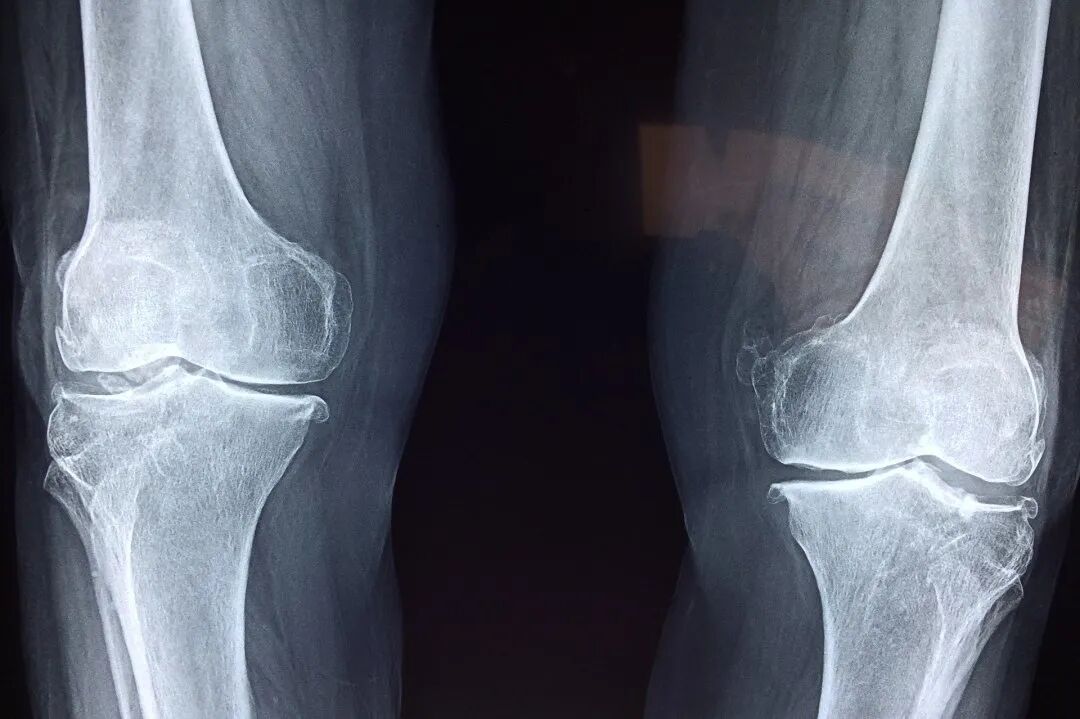

对于专业运动员来讲,在训练及比赛过程中出现运动损伤早已成为常态,如肌肉、肌腱、腱鞘、筋膜、皮肤、韧带、滑膜、滑囊等的拉伤、扭伤、挫伤。以半月板损伤为例,半月板损伤是最常见的运动损伤且难以治愈。半月板所处特殊部位 , 其在运动中承受压力较大 , 损伤情况多种多样。半月板缺少血管,血液供应差,营养主要由关节内滑液供给,因而半月板损伤难以自愈。

传统的微创关节镜手术会导致膝关节受力发生改变,进而增加早期骨关节炎发展的可能性。研究发现,利用干细胞治疗半月板损伤,效果或比传统的手术治疗更具有优势,无需手术,无需服药,轻轻松松便能改善半月板损伤。